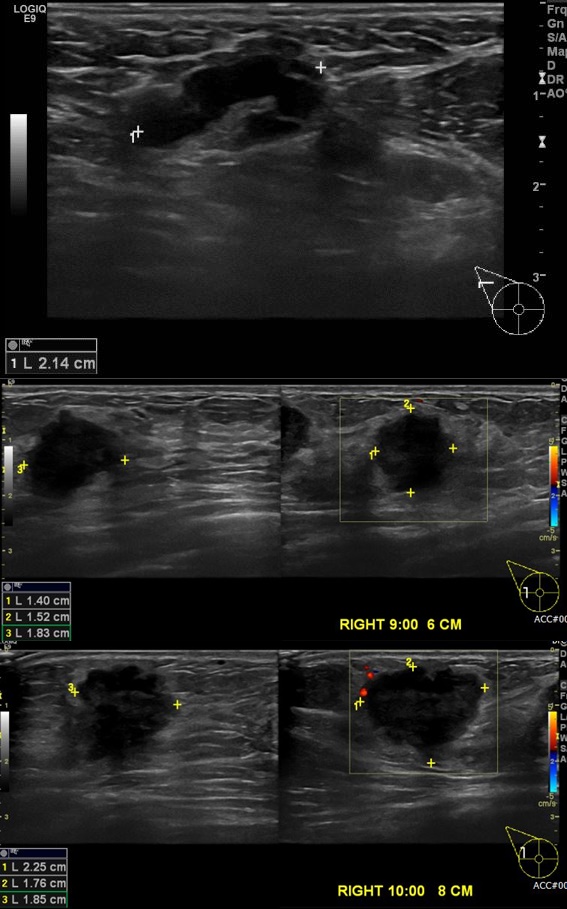

상기환자 수유맘으로 3개월 전부터 만져지는 멍울 있어 내원하신 30대 여자환자분으로

본원에서 초음파 진행후 우측유방 9시,10시,방향으로 중심핵생검검사와 우측겨드랑이 세포검사실시한결과 겨드랑이전이된 침윤성 유관암 진단되셨습니다.